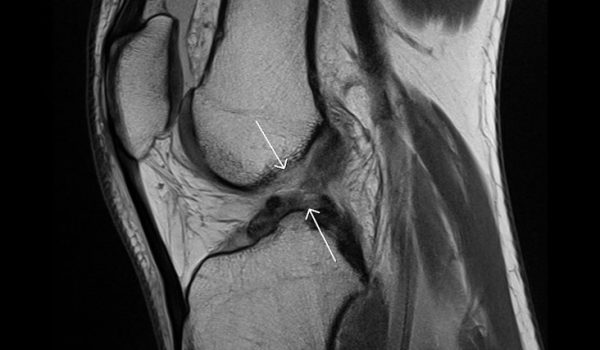

معمولا فرد زمانی که دچار این صانحه یم شود پزشک می تواند از میزان بی ثباتی زانو و دردی که بیمار دارد متوجه میزان آسیب بشود ولی معمولا برای کسب اطلاعات بیشنر و البته دقیق گرفتن یک MRI از ناحیه آسیب دیده توسط دکتر تجویز می شود. با استفاده از این روش است که می توان میزان آسیب دیدگی سایر نواحی زانو را نیز به خوبی متوجه شد. بعد از آن بسته به یمزان آسیب می توان از یکی از حالت های زیر استفاده کرد.